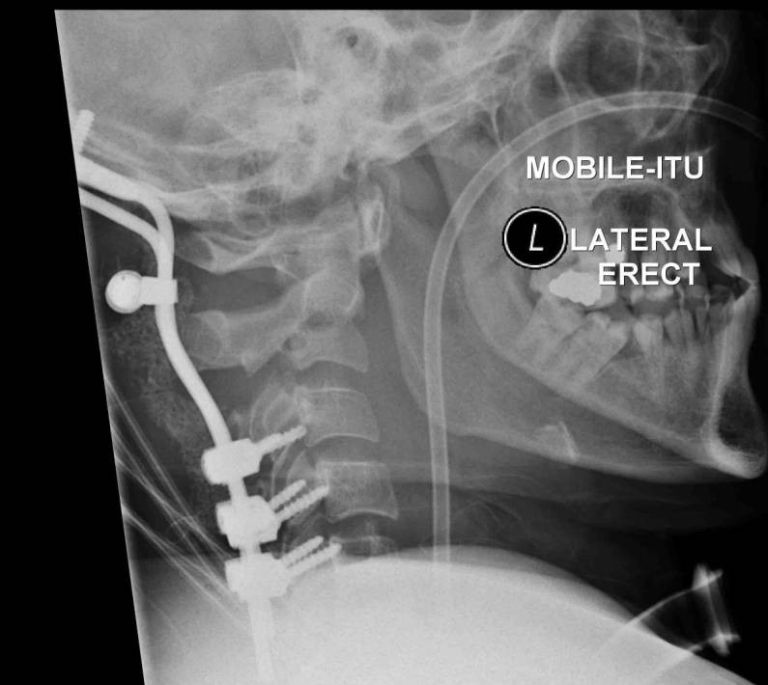

NEWCASTLE – Tony Cowan, 29 anni, è riuscito a sopravvivere, contro ogni pronostico medico, dopo che la testa è stata recisa dalla colonna vertebrale in un brutto incidente.

I tessuti muscolari hanno evitato che si staccasse dal collo dopo che la sua auto subì un brusco impatto dopo averne perso il controllo. Secondo quanto riporta Metro.co.uk, Tony, un ex muratore è riuscito a sopravvivere ma oggi è costretto a stare su una sedia a rotelle e a comunicare attraverso una macchina.